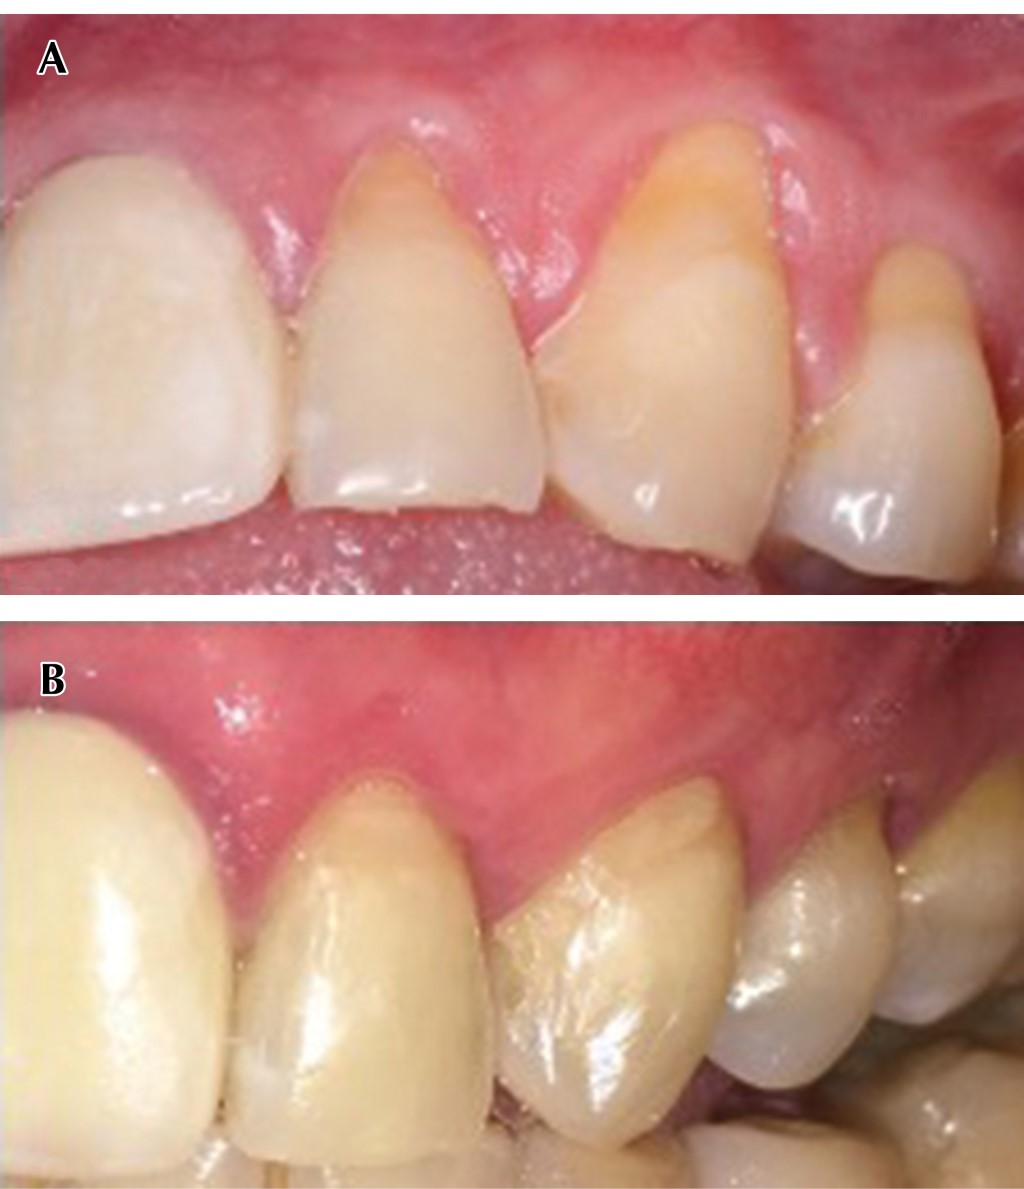

Figure 4